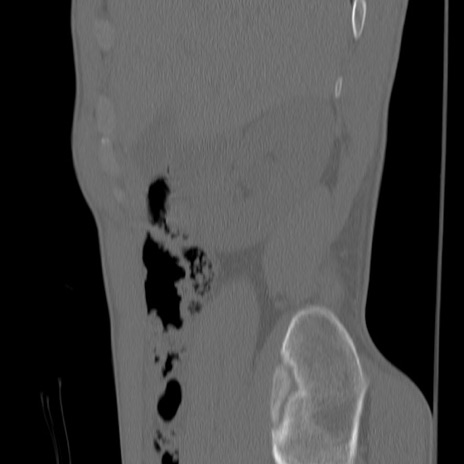

症例3 腰椎CT(矢状断像)

【症例】30歳代男性

【主訴】腰痛

【現病歴】本日旅行先で観光中に、友人と衝突し転倒し受傷。

【身体所見】麻痺なし、右下腿内側前面外側、左下腿内側に知覚鈍麻・しびれ

腰椎CT

冠状断像